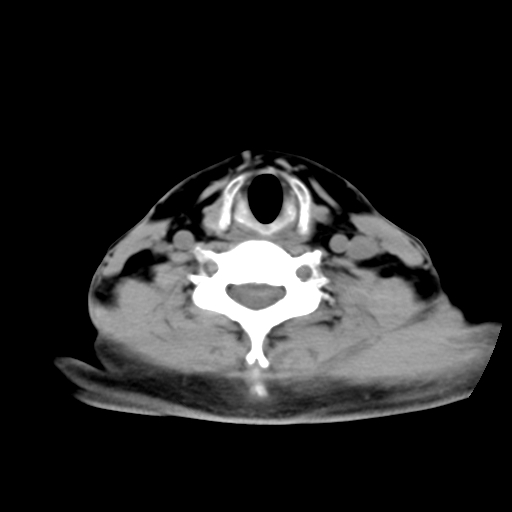

标题: CT24019:男,45岁,发现颈部肿物5个月。 [打印本页]

男,45岁,发现颈部肿物5个月,彩超示:双侧颈部及下颌部软组织增厚。

考虑双侧颈项部良性对称性脂肪增多症。